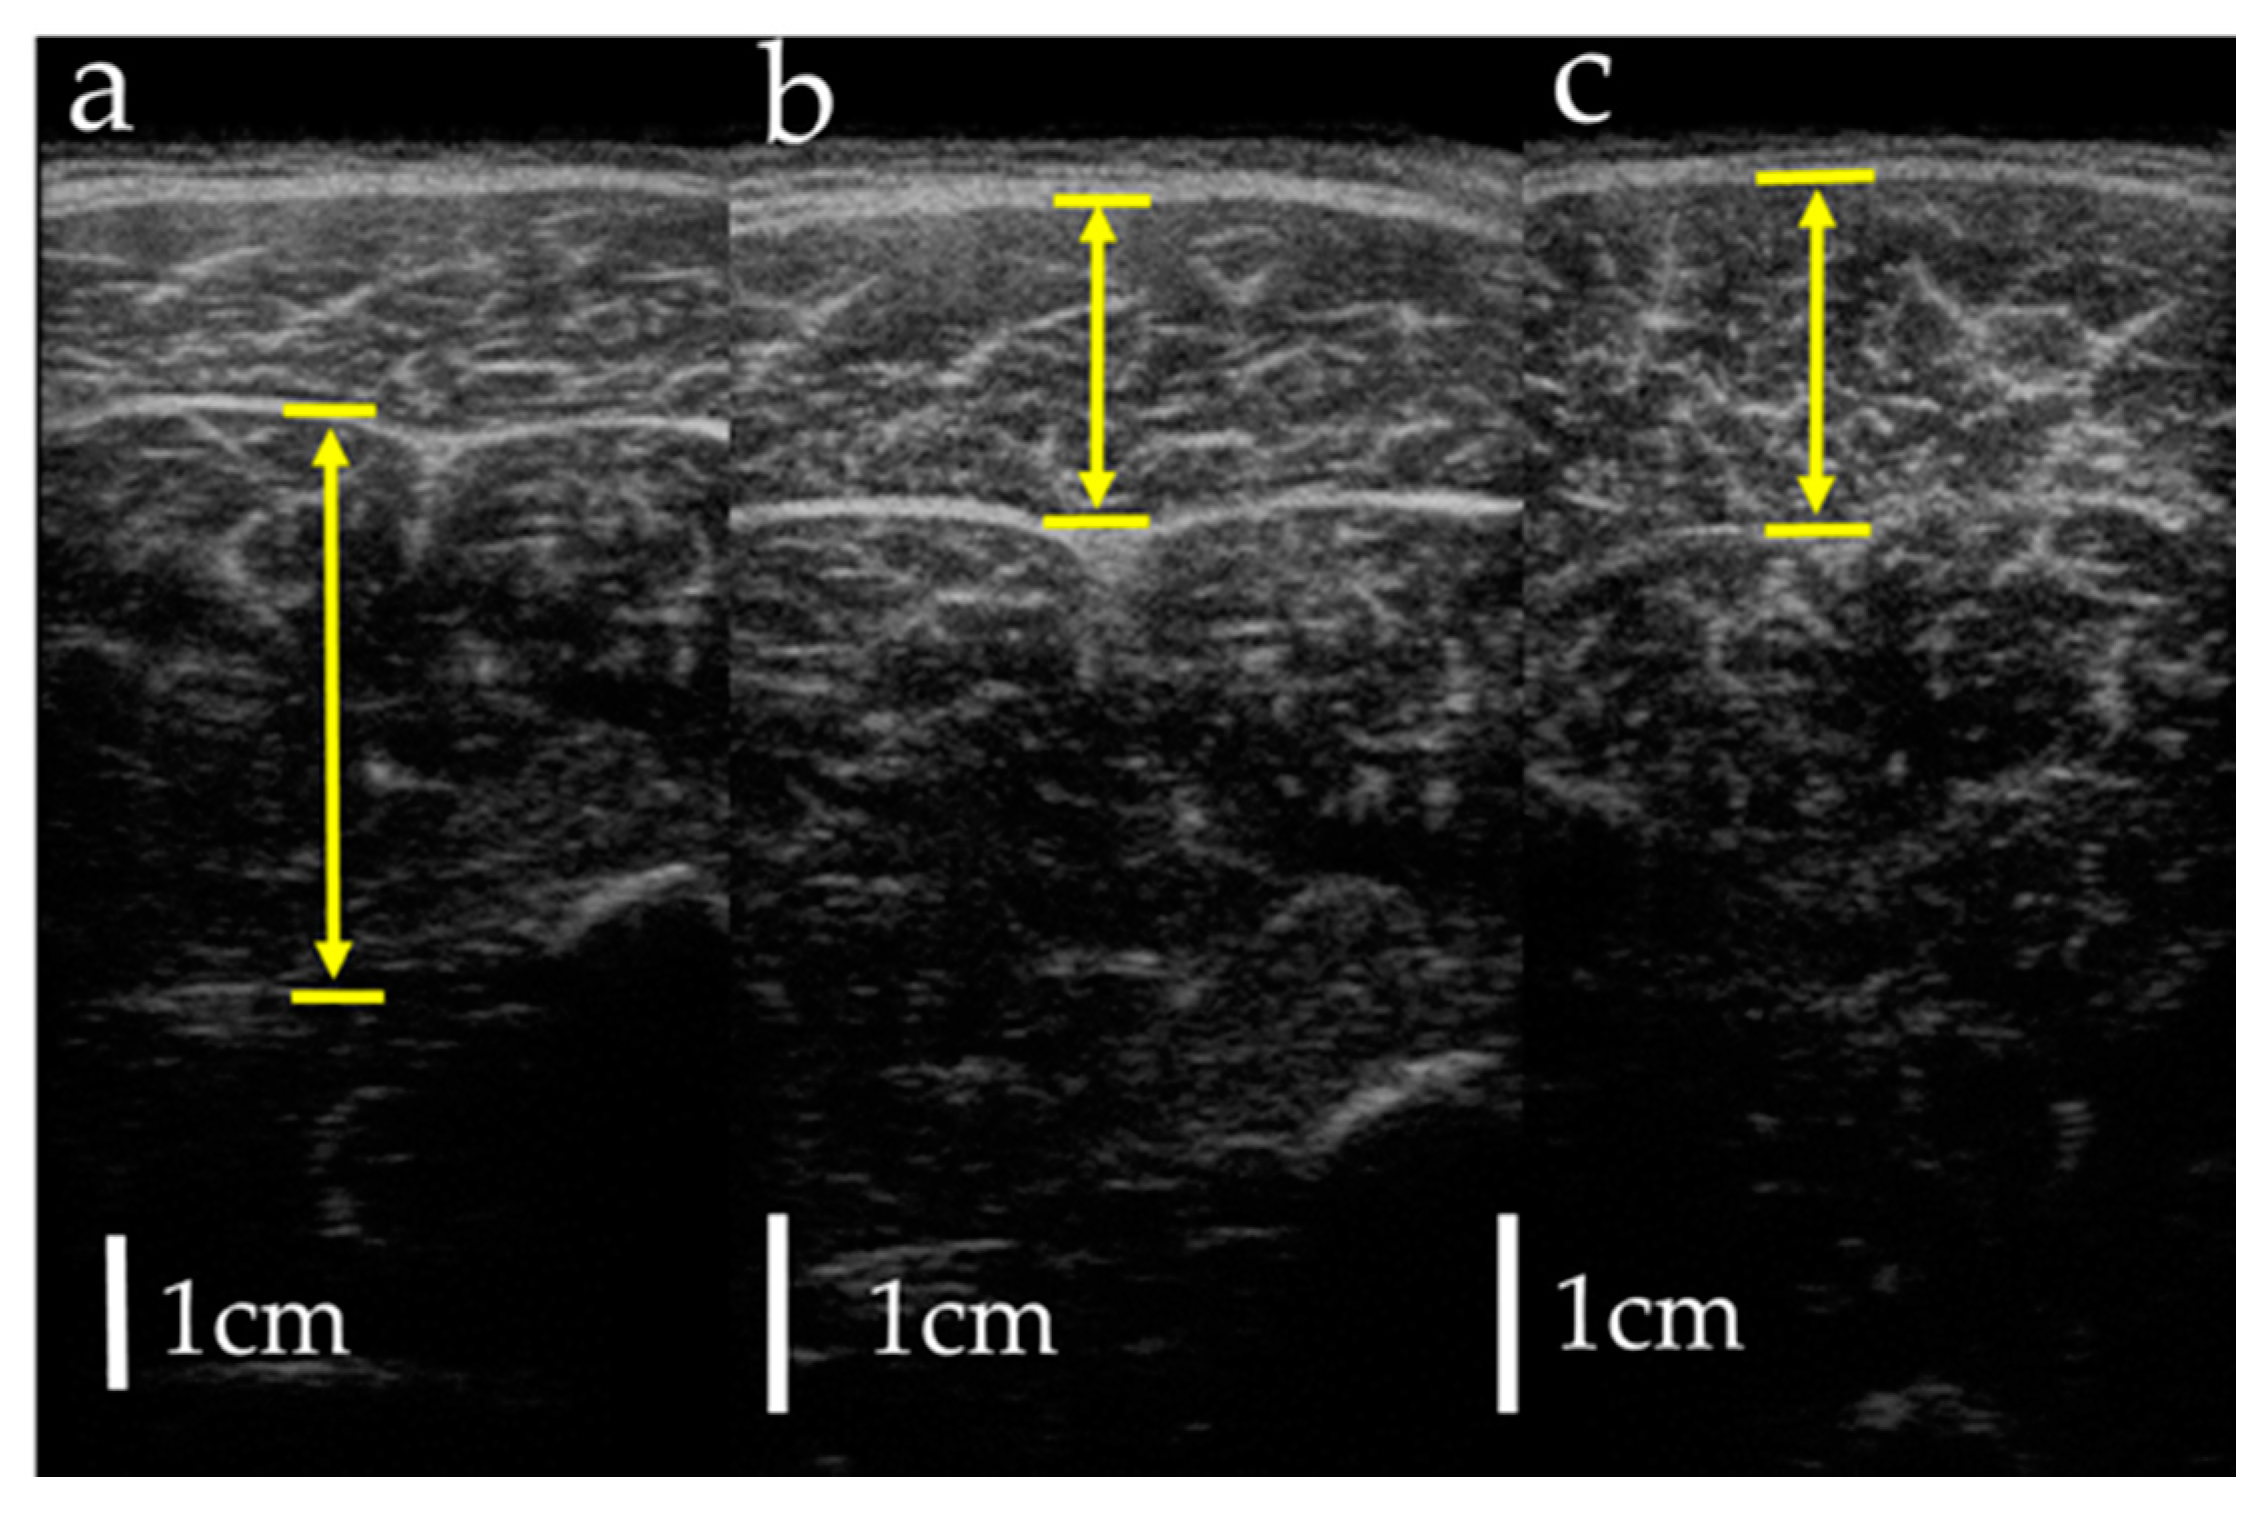

Figure 3.

Measurement of muscle thickness by ultrasonography: (a) soleus; (b) gastrocnemius lateral head; (c) gastrocnemius medial head. Arrows indicate muscle thickness.

Measurements were taken in three conditions: (1) MRI in the supine position, (2) MRI in the sitting position, and (3) US imaging in the sitting position. The sitting position was chosen for the measurement of the antigravity position because it is easy to hold the limb position with little motion in the antigravity position. In the supine position for MRI, the foot was placed on a pedestal in a supine position in which the hip and knee joints were flexed at 90°, and the foot was supported only by the heel to prevent the triceps surae from changing its shape due to contact with the pedestal. In addition, a plate was placed perpendicular to the floor at the plantar part of the foot to maintain dorsiflexion at 0°. MRI and US imaging in the sitting position were performed in a chair (with a backrest) with the knee joint flexion at 90°, the lower leg perpendicular to the floor, and the ankle joint dorsiflexion at 0° as in the supine position. In all measurements, the thigh was fixed with cushions and bands to prevent the lower leg from moving during the imaging, and the participants were instructed to hold it as much as possible. Using vertical MRI with a 0.4 T permanent magnet, (Hitachi Healthcare, Ltd., Tokyo, Japan), horizontal T1-weighted images were obtained from the fibular head to the 290 mm distal end at 10 mm intervals (Figure 1). The imaging parameters were as follows: slice plane axial; pulse sequence RF-spoiled steady-state gradient echo; field of view, 280 mm; repetition time, 110.0 ms; echo time, 8.6 ms; flip angle, 35°; slice thickness, 10.0 mm; slice interval, 10.0 mm; matrix size, 256 × 256; number of signals, average of 2; receiver bandwidth, 20.6 kHz; and scan time, 4 min and 32 s. Using the image analysis program ZedView (LEXI Co., Ltd., Tokyo, Japan), the muscles were identified based on the boundary of the fascia of the soleus (SOL), gastrocnemius medial head (GM), and gastrocnemius lateral head (GL) using the acquired images, and the areas marked on the images were measured as the MCSA of each muscle (Figure 2). The 10 mm slice areas of MRI were summed, and the volume of each muscle was calculated using a ZedView. The images of the SOL, GM, and GL were taken by US using a linear probe (7.5 MHz) in B-mode MyLab25 (Esaote, Florence, Italy). Short-axis images were taken at 20.0 mm intervals from the peroneal head in each muscle by applying a probe to the center of the ventral region of the muscle on the horizontal plane. We used a hard-type gel (LOGIQLEAN, GE Healthcare Japan, Tokyo, Japan), which is flexible and easy to keep in shape, to avoid direct contact between the probe and the lower leg. Indirect contact through the gel avoids the effects of pressure exerted by the probe on the lower leg. In addition, to maintain the position of the probe at the time of measurement, we marked the lower leg prior to the measurement, following which assessments were made based on the marking. For the measurement of MT, the maximum length of each muscle was measured with respect to the boundary of the fascia using the image analysis program Image J (Figure 3). The average value of the two measurements was calculated and used as the MT value. MRI, US imaging, and MCSA and MT measurements were performed by the same examiner.